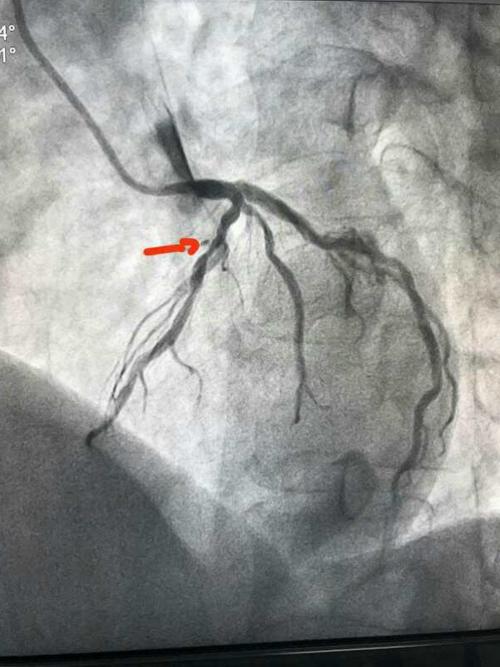

术前左前降支近段重度狭窄

(图1,左前降支近段约95%狭窄)

头位:前降支近段重度狭窄,血流变慢

箭头所示:前降支管状病变,狭窄程度大于90%,d1开口受累